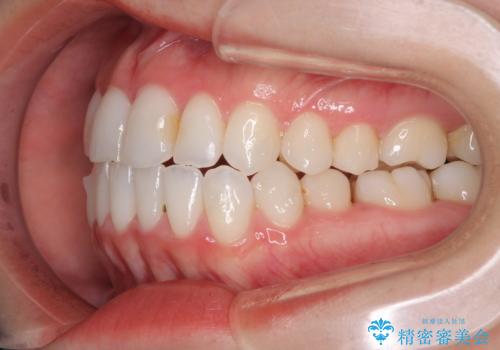

- 前歯のデコボコとクロスバイトを治したいとのことで来院された患者様です。

上下顎ともに歯列全体の側方拡大とIPR(歯と歯の間を削る)によってデコボコとクロスバイトが解消するように設計し、インビザラインにより治療を行うこととしました。

下顎骨の左側への骨格的なずれが強く、上下の正中の位置合わせや奥歯の咬み合わせ構築に苦労しました。